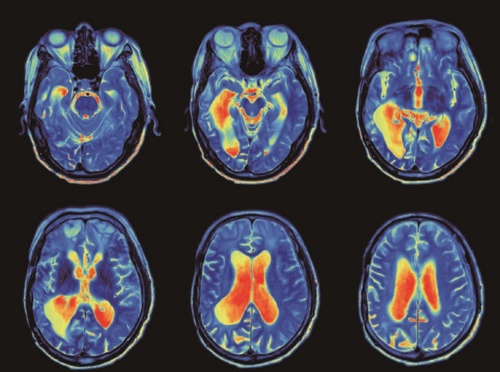

脑的MRI扫描